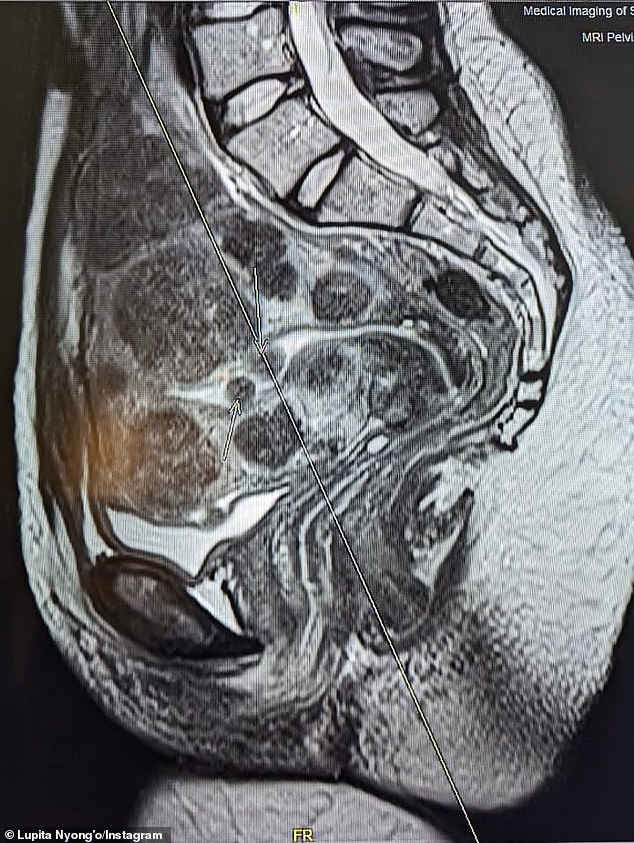

Nyong’o told her 11.3 million followers about her current health status in candor, adding an image of an MRI she had done to provide a visual aid.

‘Over the course of my lifetime, I have carried 77 uterine fibroids: 25 surgically removed, and more than 50 still growing inside me today, the largest the size of an orange,’ the 12 Years A Slave star wrote.

Nyong’o explained to her 11.3 million followers about her current health status, adding an image of an MRI she had done to provide a visual aid